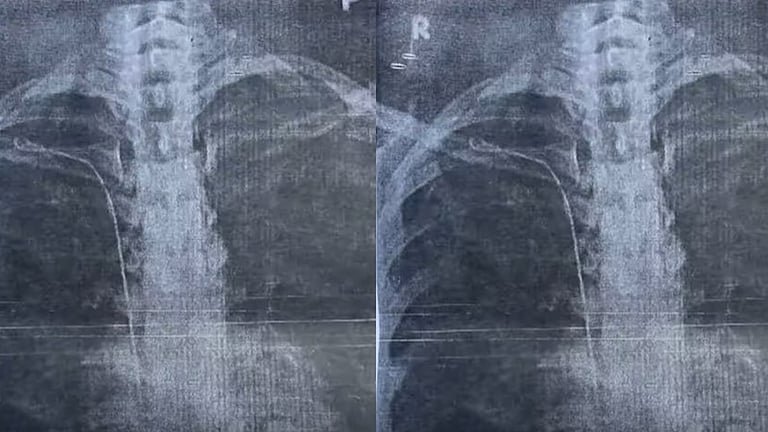

2023 മാര്ച്ച് 22ന് നടന്ന തൈറോയ്ഡ് ശസ്ത്രക്രിയയ്ക്കിടെയാണ് ട്യൂബ് കുടുങ്ങിയതെന്നാണ് യുവതിയുടെ പരാതിയില് പറയുന്നത്. ശ്വാസം മുട്ടലിനെ തുടര്ന്ന് നടത്തിയ പരിശോധനയിലാണ് നെഞ്ചില് ട്യൂബ് കിടക്കുന്നതായി അറിഞ്ഞതെന്നും യുവതി പറയുന്നു. എക്സ്റേയില് നിന്നാണ് സംഭവം അറിയുന്നത്. മരുന്നിനുള്ള ട്യൂബിട്ടവരാണ് ഉത്തരവാദികളെന്നും ഡോക്ടര് ചൂണ്ടിക്കാട്ടുന്നു. ശ്രീചിത്രയില് നടത്തിയ പരിശോധനയിലാണ് ഗൈഡ് വയറാണെന്ന് മനസിലാകുന്നത്.